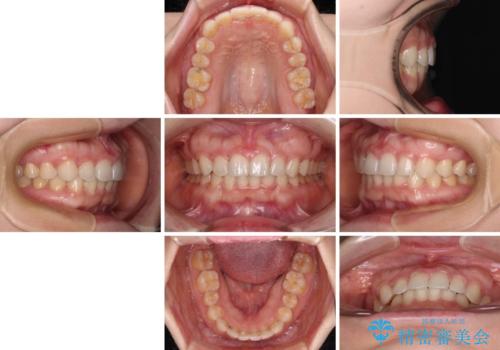

ギリギリとなりましたが、結婚式直前にワイヤー装置を外すことができました。

ワイヤー装置除去後に細かい部分を短期間のマウスピース矯正にて仕上げました。